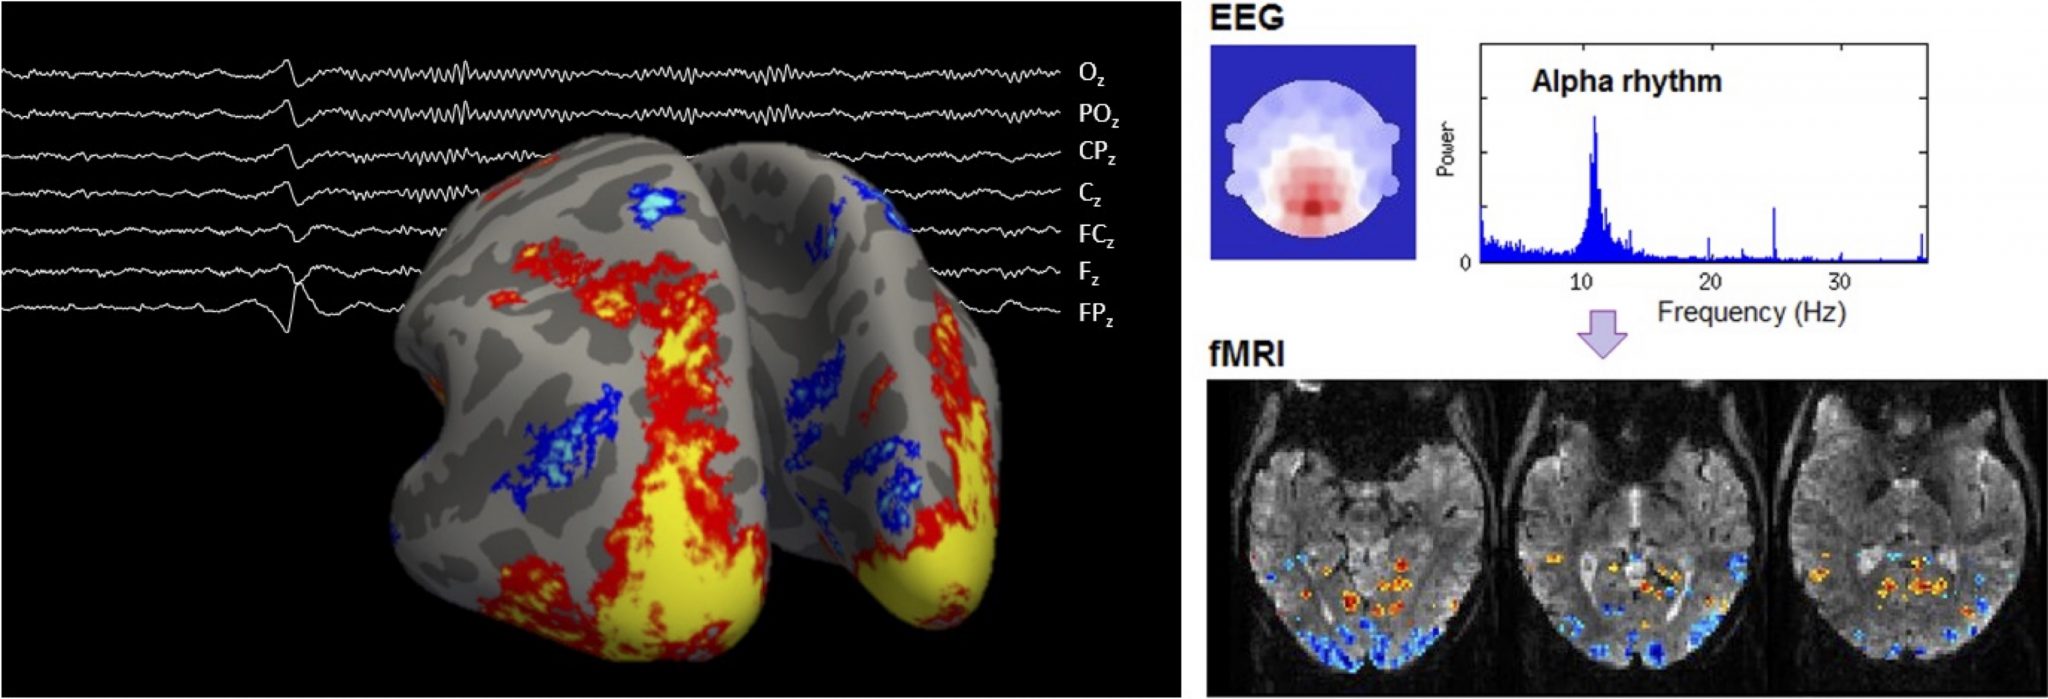

8. Multimodal imaging of brain function at ultra-high spatial & temporal resolution with combined EEG-fMRI at 7T

Electroencephalography (EEG) and functional magnetic resonance imaging (fMRI) are valuable brain imaging tools that can detect, respectively, electrical and vascular changes that occur during brain function, non-invasively. We work on the combination of these techniques at a magnetic field of 7T, where fMRI has strong boosts in sensitivity, enabling unprecedented levels of spatial and temporal specificity. Within this domain, several lines of research are open for study :

– Methodology-oriented: Both EEG and fMRI can be affected by important degradation effects when acquired together, especially at 7T. Dedicated improvements at the level of the signal acquisition and/or signal processing and analysis are vital to obtain high-quality data.

– Application-oriented: Our unique, optimized datasets allow studying subtle features of brain function such as thalamocortical interactions and cortical layer-specific activity, which remain largely unexplored. This can be investigated using cutting-edge signal processing and analysis techniques, to be adapted to these unique datasets.

Within this range of topics, MSc projects can be planned and flexibly adapted to the student’s background and interests. Motivated students are encouraged to contact us to discuss available projects. These projects are held in collaboration with CSEM.